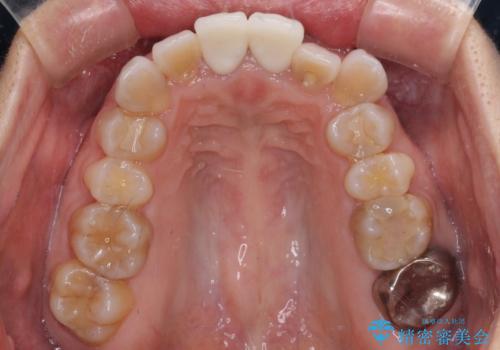

- 変色した前歯2本を気にして来院された患者様です。

右側の前歯は根管治療を行い、その後2本とも歯質に近い素材の土台を植立してオールセラミッククラウンにて補綴することとしました。

神経を取り除いた歯は、経年劣化により変色してしまいます。

前歯は審美的に、奥歯は強度的に問題が起きるため、早めにクラウンを装着することが望ましいとされています。